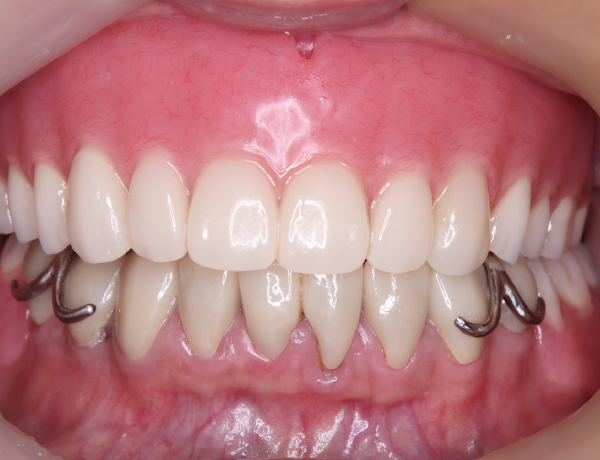

お口の中

上あご

お口の中に入っても、金属の部分がだいぶ広くとってあるのが分かるかと思います。口蓋隆起と言われる骨の部分が当たると痛みが出るので、少しその部分はリリーフして隙間を与える工夫もしています。

下あご

左右のかみ合わせも非常にバランス良く噛ませています。また、バネの部分を上の歯が噛み込まないように工夫をしています。良くこのバネの部分で折れてしまう場合がありますので、それを考慮してあります。